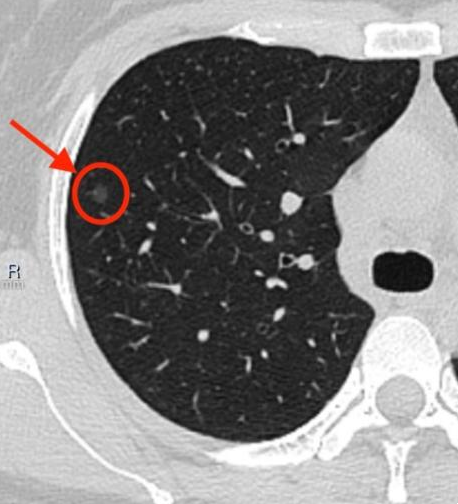

右上肺结节